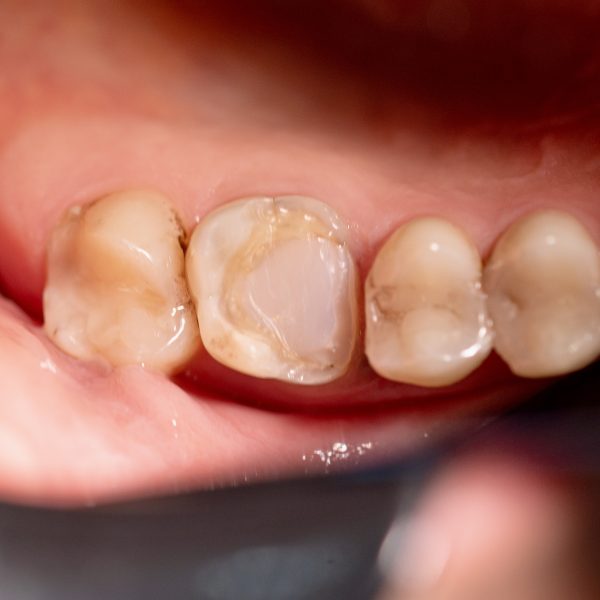

inlay&onlay glass ceramic (multi layer) cad

اینلی و آنلی یا اصطلاحا اینله و آنله نوعی درمان ترمیمی دندان هستند اینها نوعی روکش محسوب می شوند که در مواقع پوسیدگی و شکستگی دندان از آنن ها استفاده می شود. احتمالاً شنیده اید که روکش‌ها یا مواد پرکننده برای پر کردن حفره‌ها و پوسیدگی دندان قرار داده می‌شوند. با این حال، ممکن است در مورد برخی از جایگزین‌ها مانند اینله و انله دندان نشنیده باشید. فرق اینله و آنله در این است که برای پر کردن حفره های کوچک از اینلی و پر کردن حفره های بزرگ تر به طوری که لبه ی دندان را هم شامل شود از آنلی استفاده می شود. این قطعات با توجه به قلبی که از دندان گرفته شده، در لابراتوار ساخته و بر روی دندان نصب می شوند.

اینلی و آنلی شبیه به روکش های تمام سرامیک هستند اما تراش آنها بسیار کمتر از روکش بوده و در واقع روکش نصفه هستند. اینلی و اونلی برای درمان دندان هایی که نسج زیادی از دست داده اند و امکان ترمیم مناسب آنها به طور مستقیم با کامپوزیت نبوده و در عین حال نسج آنها آنقدر ضعیف نشده که نیازمند روکش باشند، استفاده می شود.

معمولاً از پرکننده‌ها برای پر کردن حفره‌های کوچک استفاده می‌شود، در حالی که از روکش‌ها زمانی استفاده می‌شود که پوسیدگی عمیق‌تر باشد یا اگر شکستگی بزرگ‌تری برای پوشاندن وجود داشته باشد. با این حال، ممکن است شرایطی وجود داشته باشد که پرکردگی کافی نباشد و روکش برای محافظت از پوسیدگی دندان بیش از حد باشد. اینله و آنله دندان همان چیزی است که بسیاری از متخصصان دندانپزشکی اگر به چیزی «درست» برای پر کردن این شکاف‌ها نیاز داشته باشند، از آن استفاده می‌کنند. آنها از پرکننده‌ها مهم تر هستند، اما به اندازه روکش نفوذی نیستند، که ممکن است به نوعی شامل تغییر شکل دندان‌ها شوند.